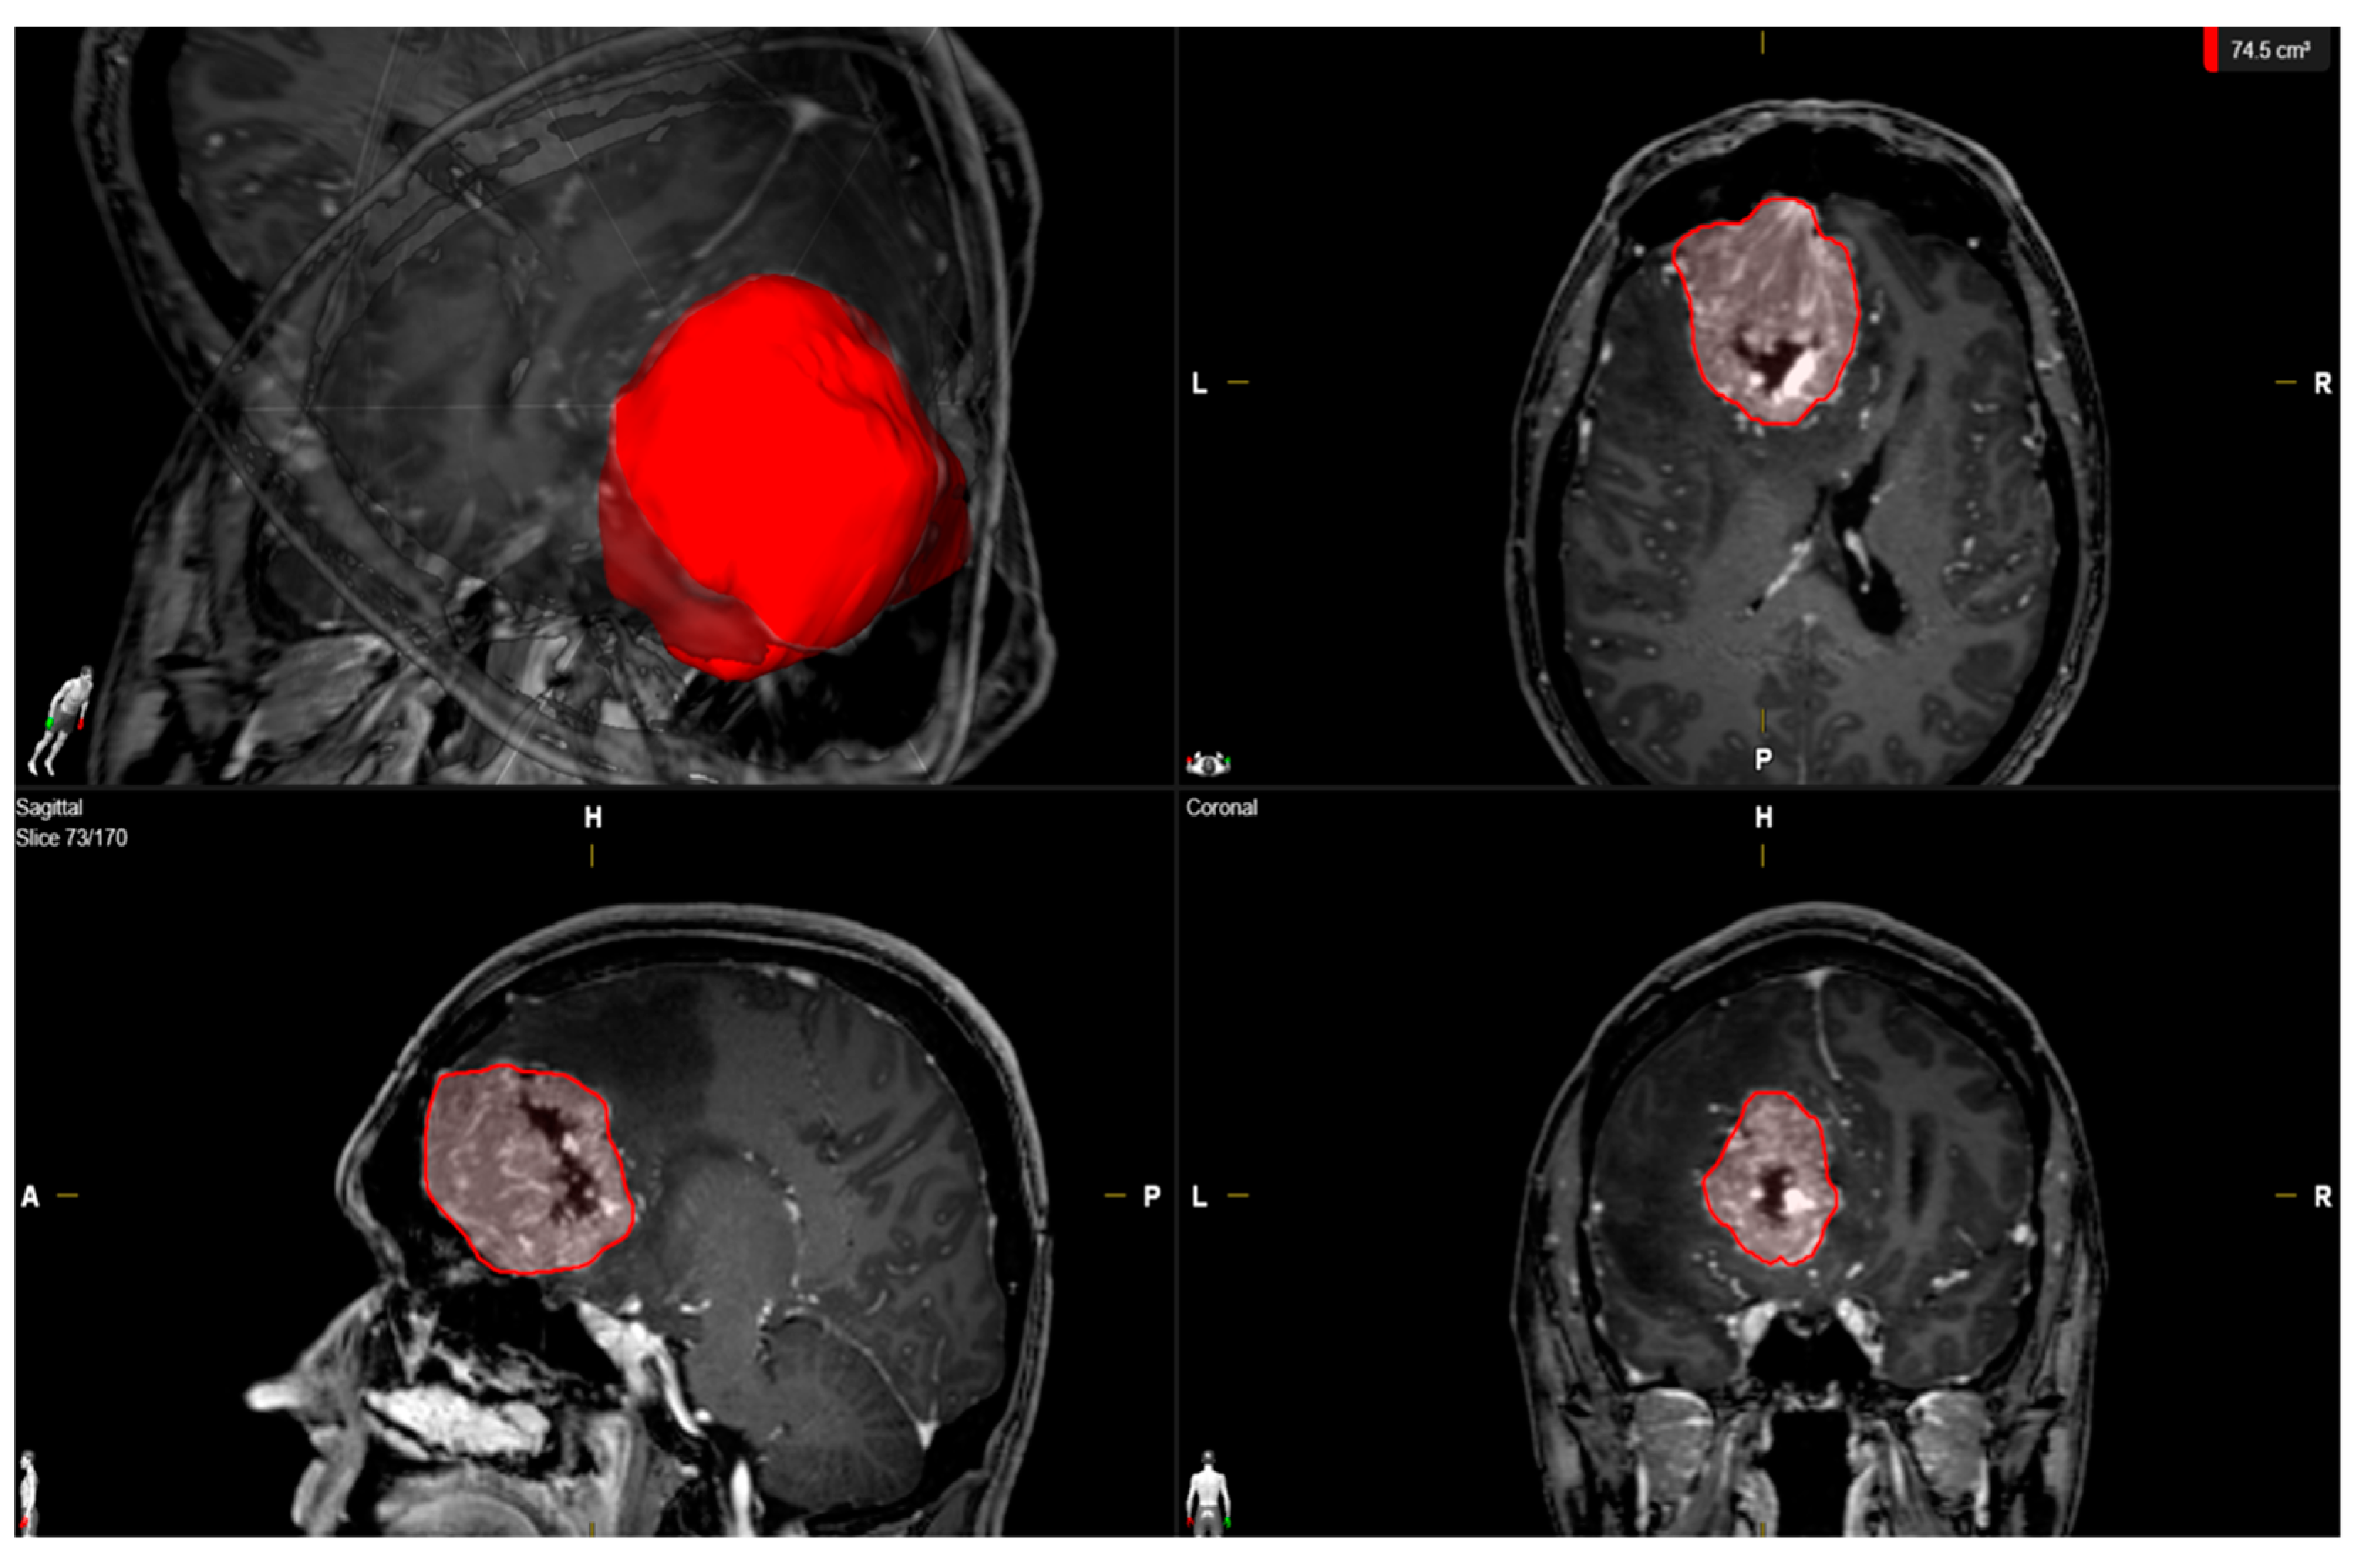

| Median baseline tumor volume (cm3, 25th–75th percentile) | 46.0 (22.4–72.4) |